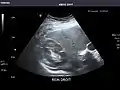

Abdominal Ultrasound (Full Exam)

STRUCTURED REPORT

(Technique: Transabdominal ultrasonography; Device: Toshiba Aplio XG)

Liver: Diffusely homogeneous and normal in echogenicity. No focal mass or contour nodularity. No intrahepatic biliary ductal dilatation.

Portal Vein: Patent main portal vein.

Gallbladder: No stones, wall thickening, or pericholecystic fluid.

Common Bile Duct: Nondilated measuring 1.3 mm at the level of the porta hepatis.

Pancreas: Visualized portions unremarkable.

Spleen: Normal in size.

Kidneys: Right and left kidneys measure 11.5 cm and 12 cm in length respectively. No hydronephrosis. Small left lower pole kidney cyst.

Ascites: None.

Aorta: Visualized portions normal in caliber, 16 x 15 mm.

IVC: Normal.

IMPRESSION:

Normal abdominal ultrasound.